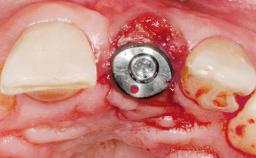

Immediate Flapless Placement of an Implant in a Maxillary Right Lateral Incisor Site

This 43-year-old male patient, a non-smoker, came to our practice because of a fracture of tooth 12 caused by a bicycle accident. Due to the combined para- and infrabony crown and root fracture, tooth extraction, and subsequent implant placement were suggested to the patient as the therapy of choice. The patient had high esthetic expectations with regard to the treatment outcome and asked for an immediate fixed provisional restoration. His individual esthetic risk profile summed up to a medium esthetic risk.

Placement Protocol Immediate implant placement

Tooth Site Maxillary incisor or canine

Socket Morphology Single-root socket

Socket Integrity Sufficient, with intact bone walls

Bone Volume Sufficient, with intact walls